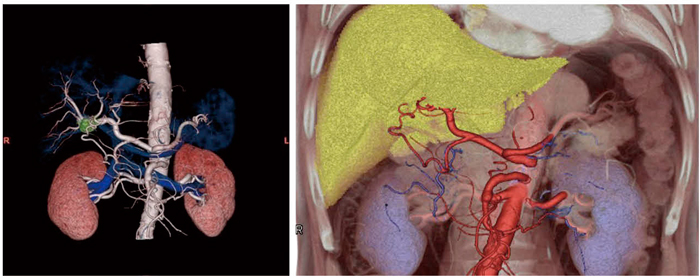

例えば,“CT腹部大動脈瘤解析”では腹部大動脈にワンクリックでパスを作成し,簡便に動脈瘤の拡張率等を計測できる。“CT肝動脈塞栓術ガイド”では,VRやSUMで肝動脈塞栓術に必要な解剖学的情報(血管や骨)とカテーテルのルートを表示する手術ガイド画像を作成する。“CT下肢末梢動脈疾患解析”では,末梢動脈疾患(PAD)などの腹部〜下肢までの広範囲のCTデータを観察するために,血管の観察に不要な骨を自動除去し,血管のセンターラインを自動で作成する。微細な血管まで描出することが可能である。すでに実績のある“CT大腸解析”では,今般さらに機能の改良や新機能の追加を行い,2体位同時表示やパスの抽出精度などを強化した。

図1 高度な画像解析をサポートする多彩なプロトコル

a:CT腹部大動脈瘤解析 b:CT肝動脈塞栓術ガイド c:CT下肢末梢疾患解析 d:CT大腸解析